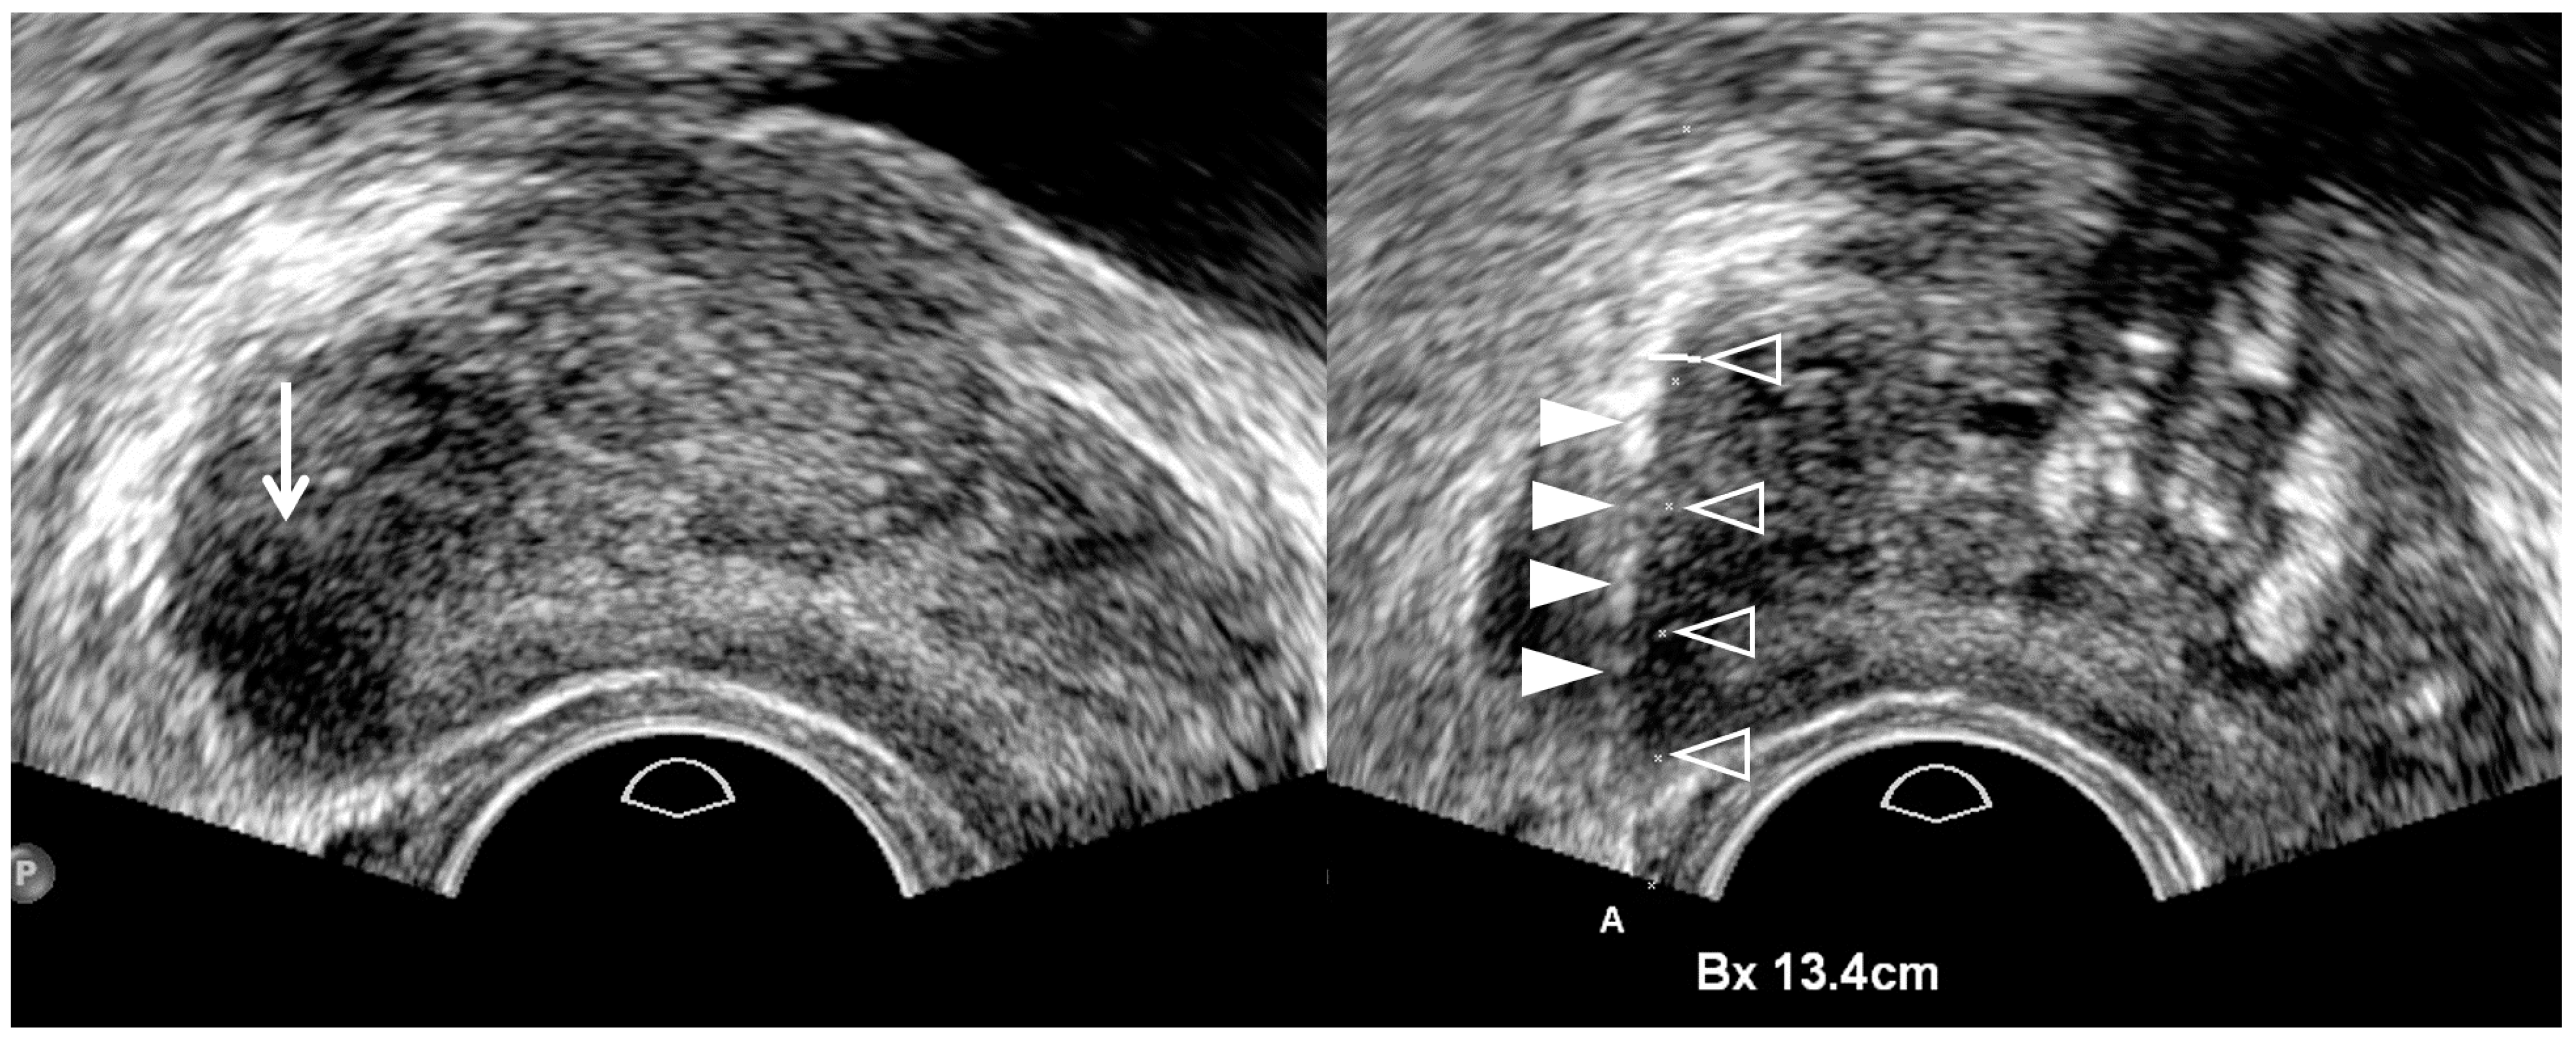

| Tumor Location/Morphology | MRI | TRUS |

|---|---|---|

| Scan axis to urethra | Perpendicular | Oblique |

| Anterior 1/3 location | Base and mid-gland | Mid-gland and apex |

| Middle 1/3 location | Same location | Same location |

| Posterior 1/3 location | Apex and mid-gland | Mid-gland and base |

| Tumor size | Different size | Different size |

| Tumor shape | Different shape | Different shape |